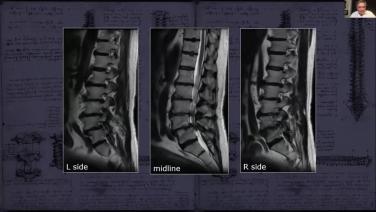

The 123s of Minimally Invasive Approaches through Case Presentations with Roger Hartl, MD